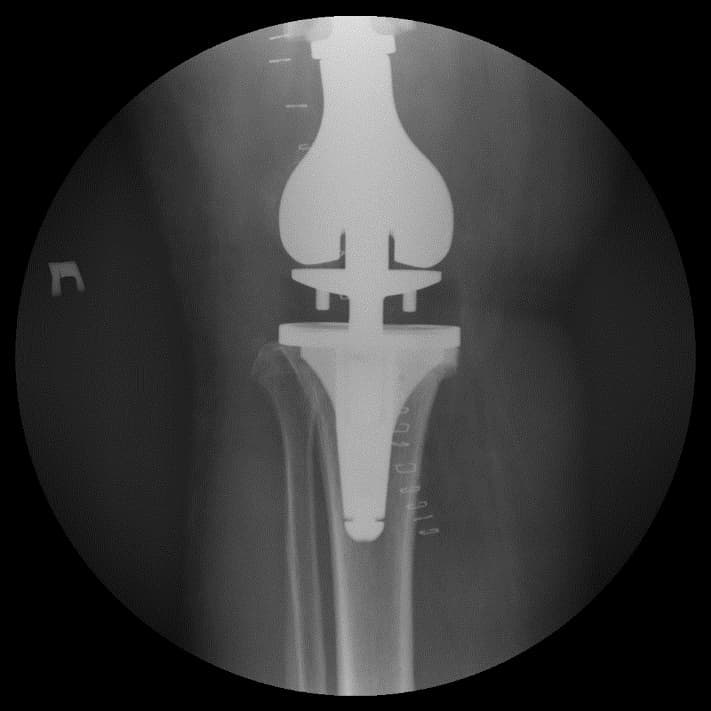

Өвдөгний үений шөрмөсөн холбоосууд үрэвслийн улмаас бүрэн гэмтсэн Дунд чөмөг - шилбэ ясны 3 зэргийн дутмагшилтай учир дунд чөмөг-өвдөгний хавдрын протез сонгон суулгасан. Энэ дунд чөмөг-өвдөгний хавдрын протезын онцлог нь шилбэ болон дунд чөмөгний хэсэг нь хоорондоо давхар холбогдох нугас буюу hinge system-тэй юм. Hinge system нь үений холбоосын үүргийг гүйцэтгэн – үе хоорондын зайг барих, үений тогтвортой байдлыг хангах зорилготой.

Үе дайрсан ясны анхдагч хавдар, ясны дутмагшлын үед хийгдэх мэс засалimg15Үе дайрсан ясны анхдагч хавдар, ясны дутмагшлын үед хийгдэх мэс засалimg16

Зураг 3. Мэс заслын дараах рентген зураг. Эгц урд, хажуугаас авсан байдал

Өвдөгний үений шөрмөсөн холбоосууд үрэвслийн улмаас бүрэн гэмтсэн Дунд чөмөг - шилбэ ясны дутмагшилтай учир дунд чөмөг-өвдөгний хавдрын протез сонгон суулгасан. Энэ дунд чөмөг-өвдөгний хавдрын протез нь мөн hinge system- тэй.